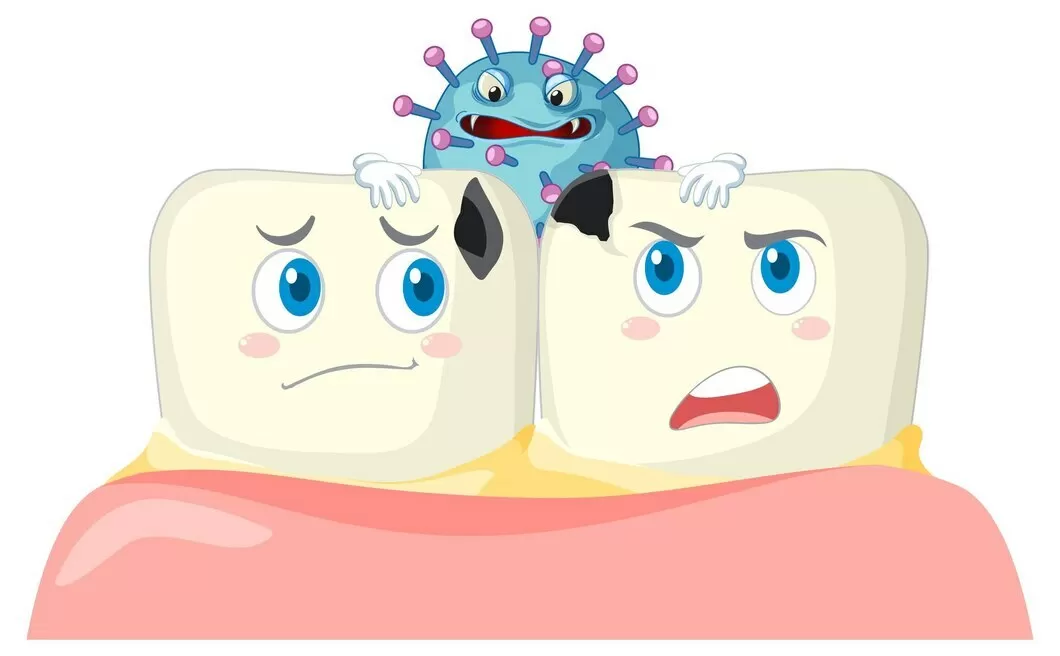

Лучшая защита — гигиена полости рта

Еще одной важной причиной возникновения заболевания является недостаточная гигиена полости рта. Если вовремя не почистить зубы, во рту начинают размножаться болезнетворные микробы и налет, в результате чего меняется кислотно-щелочной баланс.

Стоматологи наблюдают активизацию кариеса после перенесенных общих заболеваний. Ведь любая болезнь ослабляет иммунитет человека, что, в свою очередь, способствует возникновению и развитию кариеса.